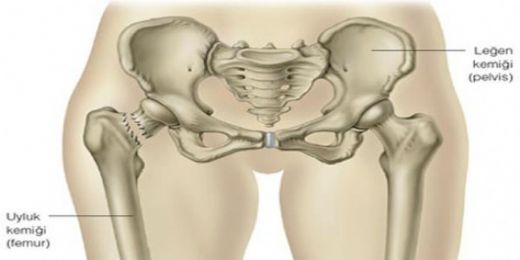

• Pelvik kemikler

• Destek: Bu kemikler, vücuda yapısal destek sağlar. Özellikle pelvis, vücut ağırlığını taşımak için kritik bir rol oynar.

Pelvis Kemiği Önemi